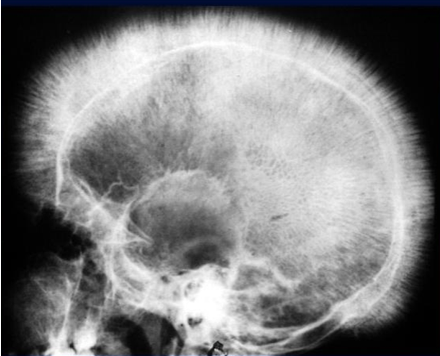

- Plain skull X-ray: May show the classic “hair-on-end” appearance.

- X-ray - bone marrow hyperplasia, Skull – interrupted porosity gives hair on end appearance

z In the skull, there is widening of the diploë and there may be perpendicular striations giving an appearance known as ‘hair-on-end’

Hair-on-end appearance of the skull

X-ray skull (lateral view) of a child with beta thalassemia Expansion of the diploic space with thickening of the trabeculae is the result of extramedullary hematopoiesis. The hair-on-end appearance produced can also be seen in other chronic hemolytic anemias. e.g. Sickle cell Disease

Thalassaemia haemolytic anaemia. Skull showing thickened diploë